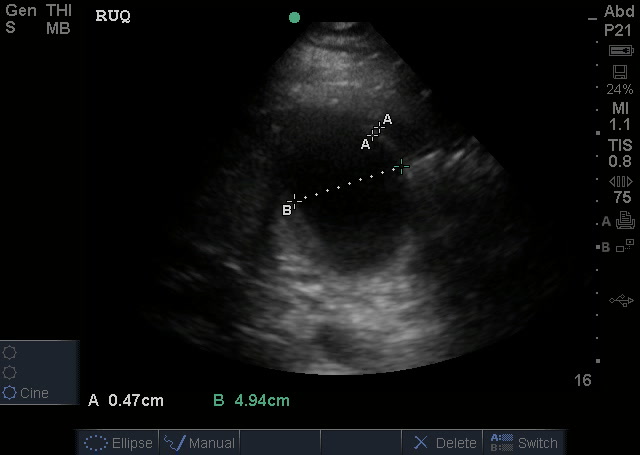

Gallbladder measurements:

The normal gallbladder measurements are an anterior gallbladder wall of 3mm, a width of 4cm and a length of no more than 9-10cm. The common bole duct (not measured) should be 6mm at the age of 60yrs (adding a mm for every decade above 60). The above image also shows a small amount of sludge but no obvious gallstone (it may have went into the bile duct and obstructed there). So, putting it together – this is obviously abnormal and evidence of acute cholecystitis.